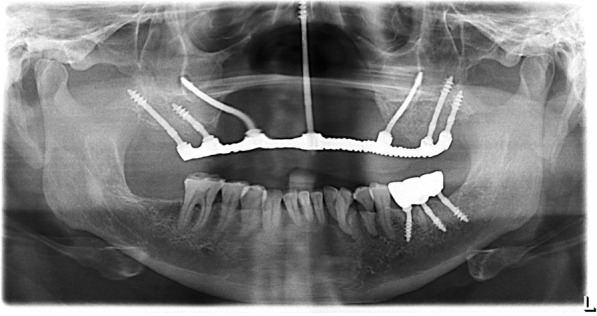

Fig. 4.

Schematic planning of the implant placement

Under local infiltration, the implants were placed in a flapless procedure, successfully engaging pterygoid apophysis and zygomatic bone bilaterally in the maxilla and achieving high primary stability > 70 Ncm as listed in Table 1 (Figs. 4, 5b, and 6a). Additionally, one zygomatic implant was used for the glabella region anchorage, engaging the floor of the frontal sinus [6]. The osteotomy for glabella was made keeping the surgically compromised upper lip in line with nasion for the future emergence profile of the glabella abutment, and implant osteotomy was made through the lip toward between the inner canthus of the eyes holding the remaining nasal bridge by fingers to perform a flapless procedure.

In the mandible, three implants were placed in order to replace the left molar (Table 1) (Fig. 6b). Jaw relation recordings were made with bite registration wax after anthropometric VD measurements, following the “equal thirds concept” [11].

a Post-operative CT coronal view: one zygomatic implant was used for the glabella region anchorage, engaging the floor of the frontal sinus, and in the mandible, three implants were placed in order to replace the left molar. b Post-operative CT sagittal view